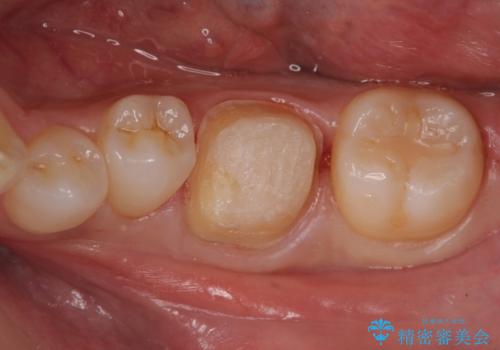

以前入れた詰め物が欠けた

- 他院で入れたセラミックインレーが欠けてしまい来院。

やり直しに当たって、以下の提案を行い選んで頂いた。

①同様にセラミックインレーのやりかえ

→欠けたところが上の歯と噛み込んでおり、そのままやりかえるとさらに歯が薄くなり、また欠けてしまうリスクが高い状態